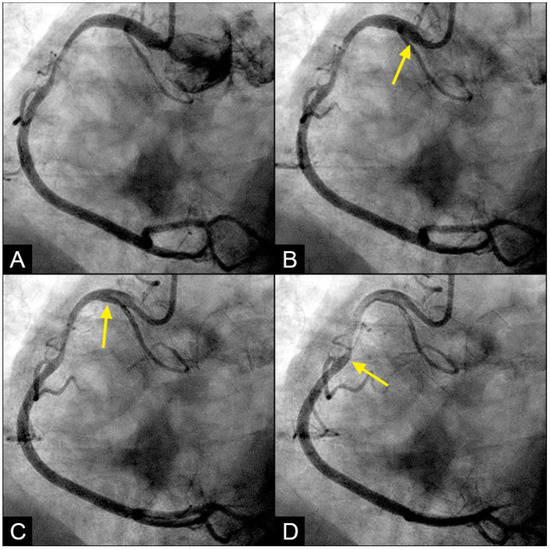

In the right coronary artery (RCA), during diastole, the blood flow could be observed over a black contrast background and identified clearly with well-organized flow and a sharp border, without mixing between blood and contrast, following the apex of the curves. By visual observation, this flow was laminar (Figure 5A–D) (Video S1).

Figure 5.

(A,B) Laminar flow. These four coronary images are in consecutive sequence. (A) This is the angiogram of the right coronary artery (RCA), which is filled with contrast (in black). (B) The blood (in white) is seen well organized with a sharp border and a pointed tip, curving along the apex (yellow arrow). (C,D) The blood (in white) is seen following the apex of the curves (yellow arrow). This is the laminar flow following the curves in a helical fashion.